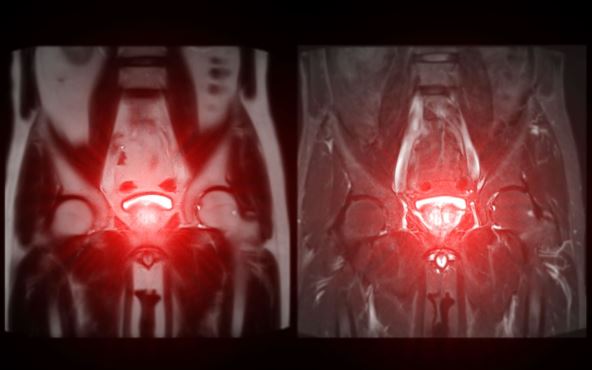

Istraživači iz Medicinskog centra za onklogiju sa Univerziteta u Klivlendu, razvijaju genetski test koji može da predvidi koji pacijenti sa rakom prostate imaju korist od spomenute terapije, a koji ne.

Ovaj test je važan za sve one sa recidivom raka nakon operacije uklanjanja prostate. Do sada su lekari odluku donosili na osnovu pokazatelja poput nivoa PSA u krvi, izgleda tumora ili vremena koje je prošlo od operacije. Ali sada su uspeli da proniknu u samu biologiju tumora, a u tome im je pomogao priručnik za rak dojke.

Iako gotovo svi tumori prostate imaju hormonske receptore, oni ne zavise od hormona na isti način. Zato su naučnici morali da razviju test PAM50 koji će meriti i prisustvo, ali i aktivnost tih mehanizama. Genomskom analizom, naučnici su uspeli da izdvoje dve grupe pacijenata.

U prvoj, tumori kod pacijenata reaguju na hormone, tako što se kod terapije testosteronom on smanjuje, a rast tumora se usporava. Dok su u drugoj grupi, pacijenti sa tumorima koji su znatno manje osetljivi na hormonsku terapiju.